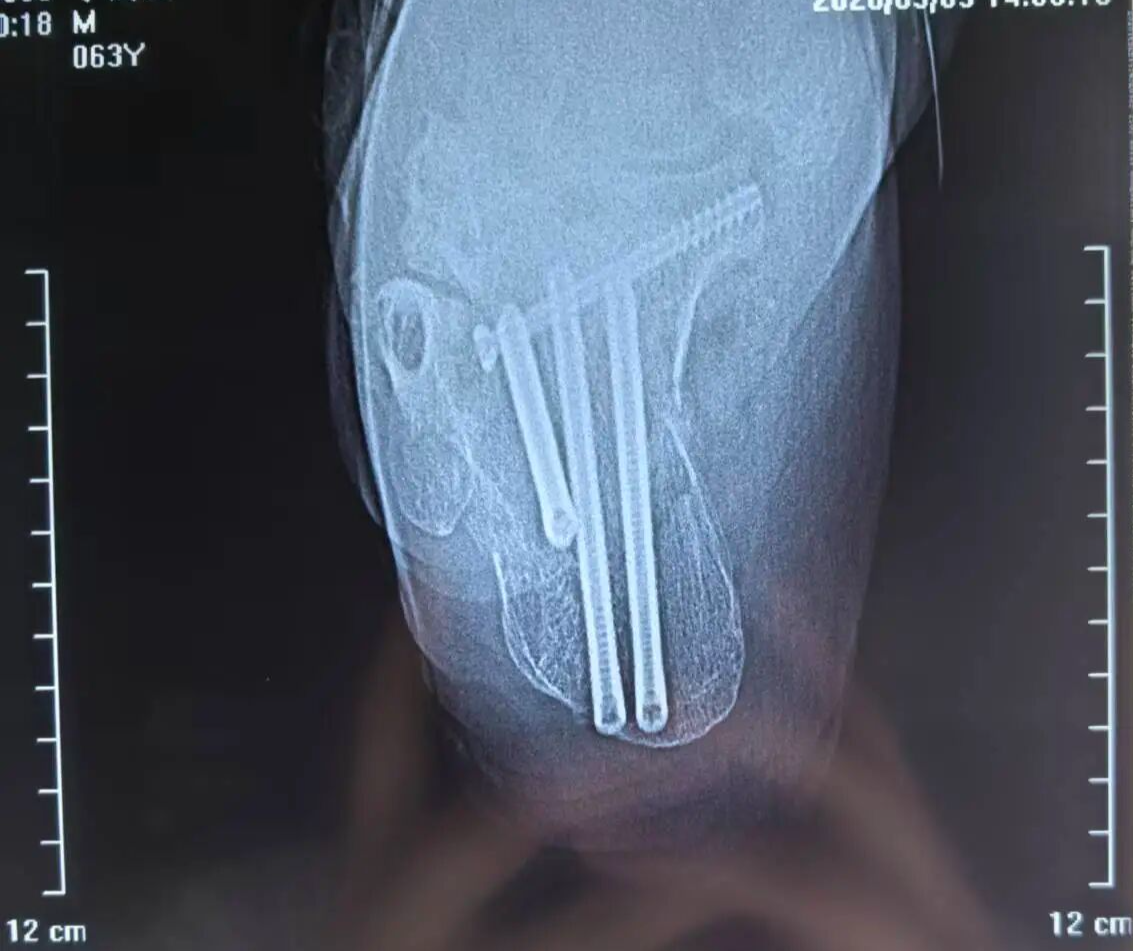

术后

日前,一名高处坠落伤致左侧跟骨粉碎性骨折的患者入院。骨三科团队经充分术前讨论,为其量身定制微创手术方案。术中在X光精准引导下,经皮撬拨复位骨折块,以空心螺钉稳固固定,出血极少、创伤小。术后患者恢复良好,早期即可开展功能锻炼,避免了传统大切口带来的并发症隐患。